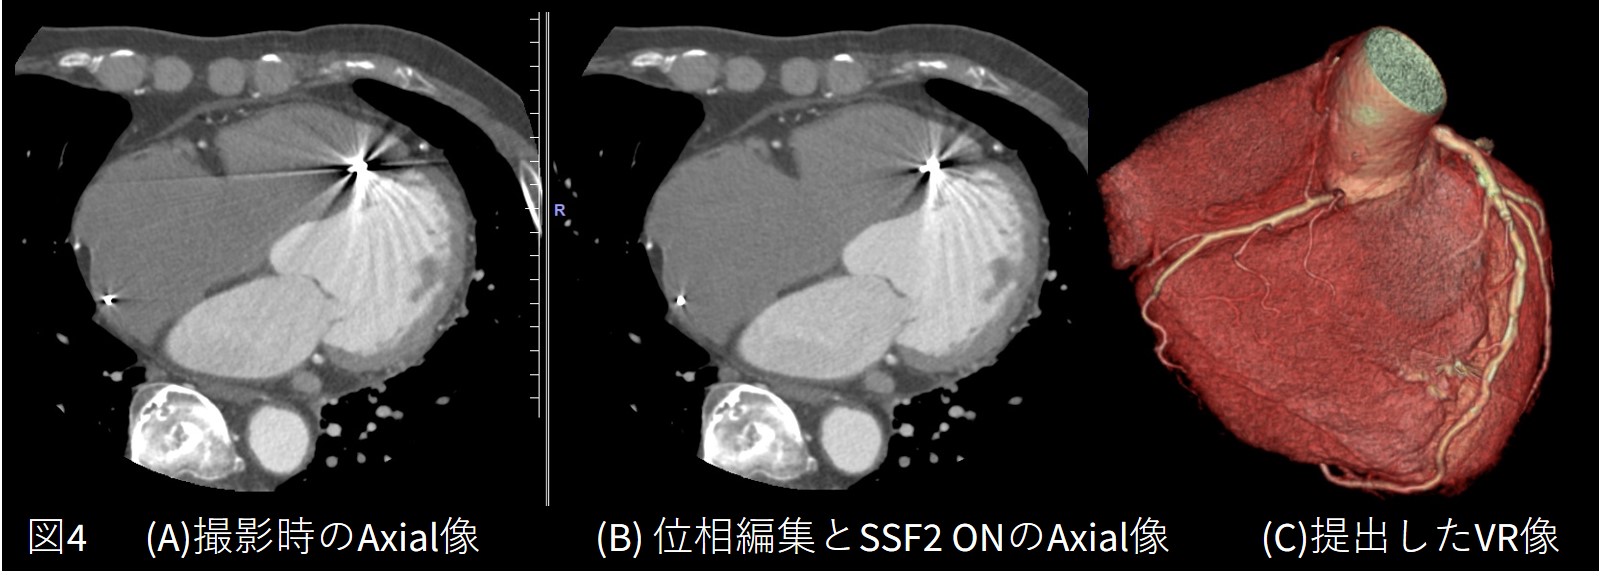

徐脈性心房細動にてペースメーカー植え込み術を施行済の症例です。撮影中に不整脈が連続して出現し、すべての不整脈データを削除してしまうと画像を作成することができず、右図の矢印に示すように1心拍を残してSSF2を使用したところ静止画像を得られました。

PMIのリードのアーチファクトの影響も少なく、LADの評価が十分にできる画像を構築でき ました。

Frontier_Kofukyoritsu06.jpg